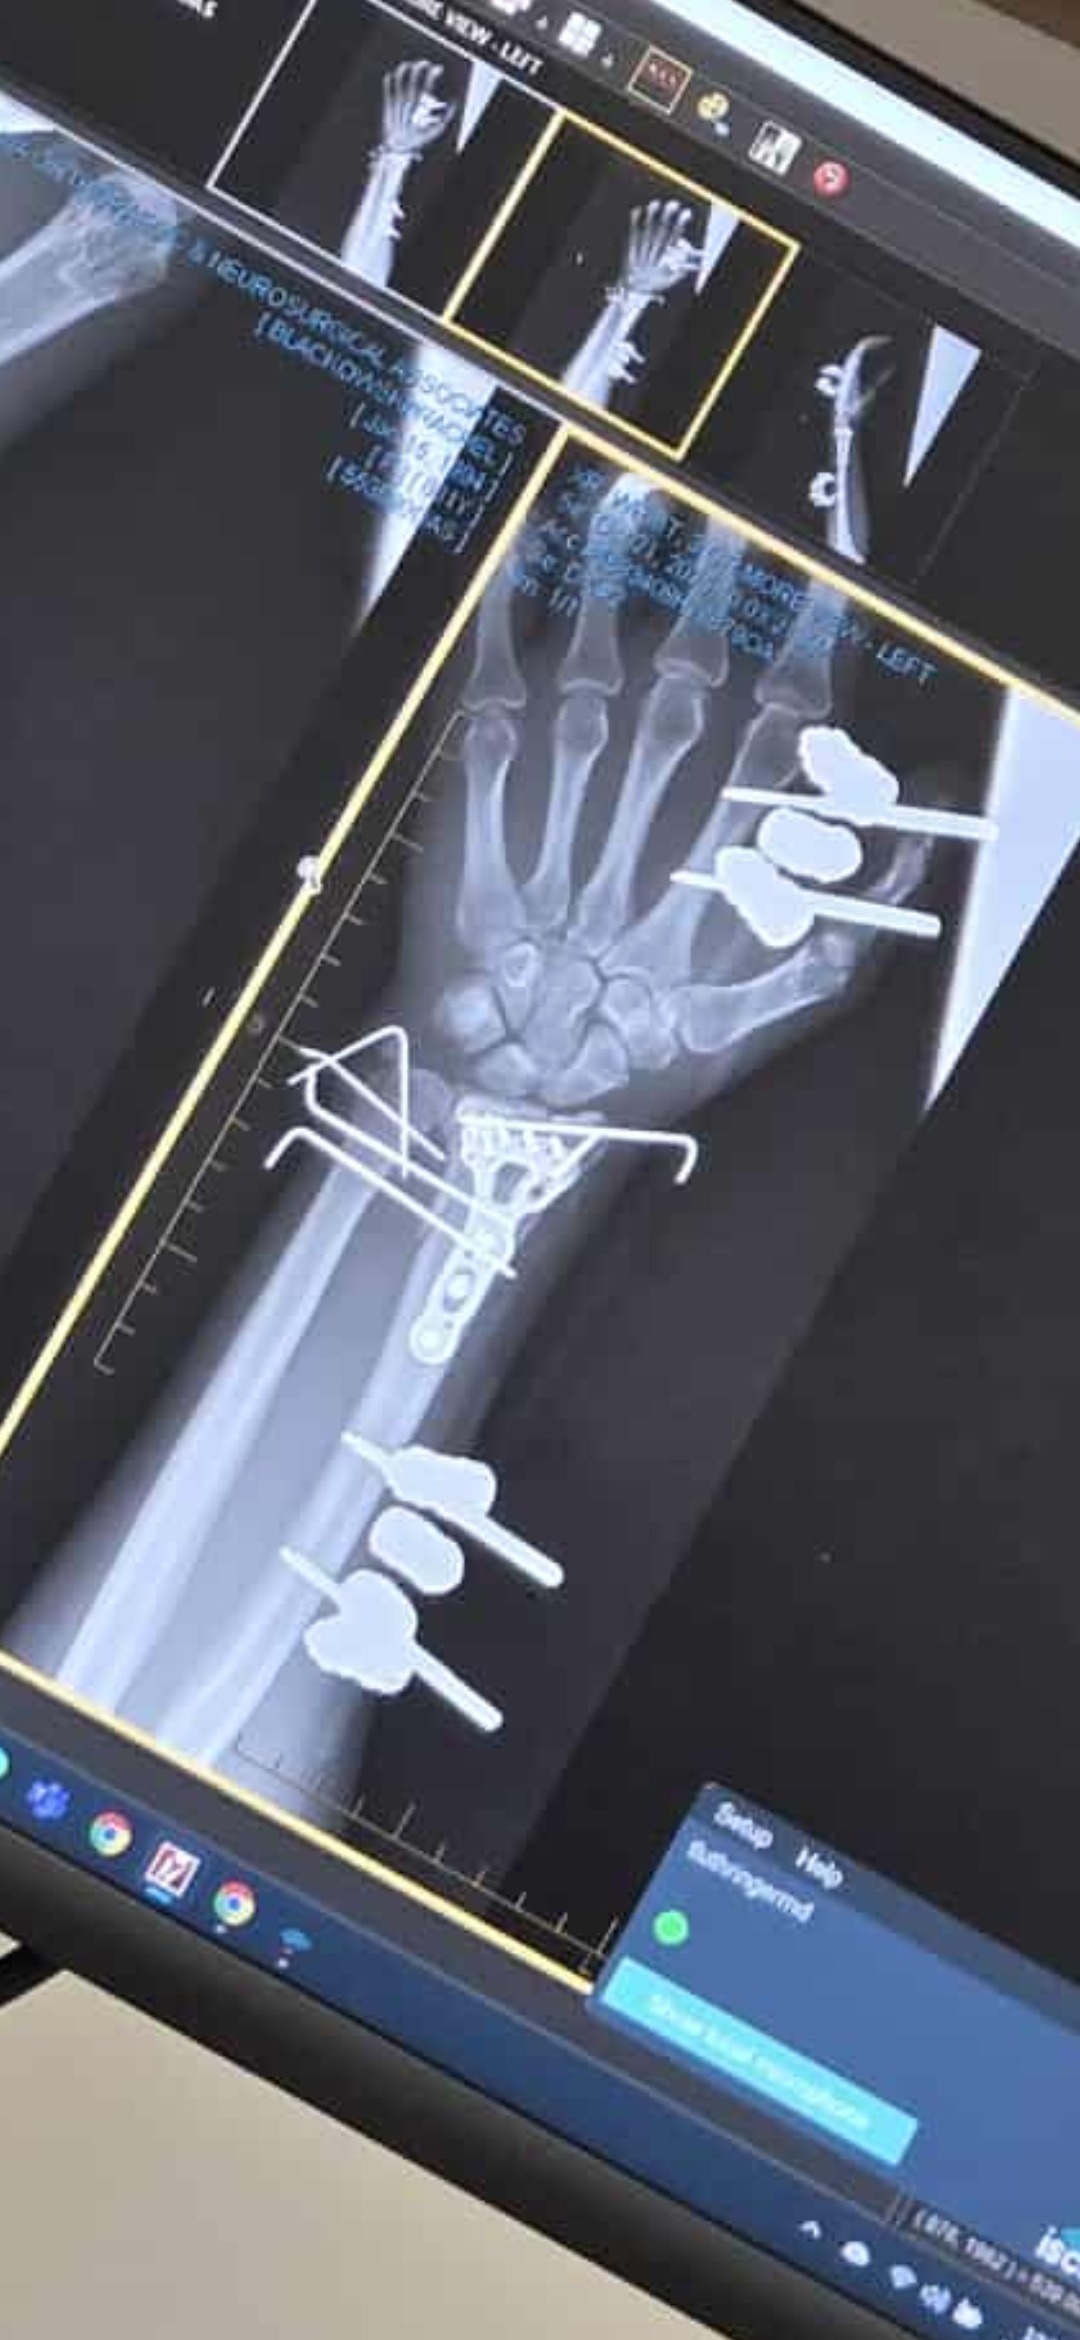

I SURVIVED!!!! My name is Rachel Blackowski, 31 years young.. I was in a severe car accident on Oct 4th . Spent a week in the hospital and have been in rehab. Broken wrist on the left hand (& I'm a lefty) Broken right leg, ankle and knee, non weight bearing injuries for both have me in the wheelchair for an estimated 12 weeks. Have gone through 3 surgeries so far with more to come. Looking at a 6-8 months minimum recovery. Unable to work to provide living wages & owe medical bills. Usually I would be too stubborn & prideful to ask for help ... but this has humbled me to realize I need to lean onto others in my time of need and it is okay. Thank you for any help offered.